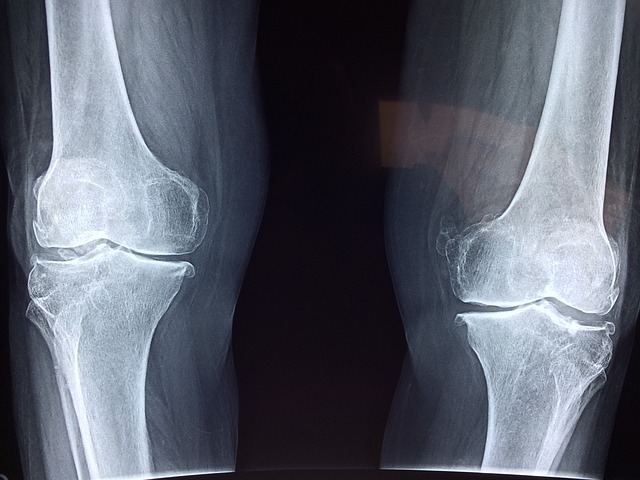

1)퇴행성관절염

가장 흔한 관절염 유형으로 연령이 높아질 수록 발생하는것이 특징입니다.

관절 연골의 손상이나 퇴행성 변화로 인해 염증과 통증이 생깁니다.